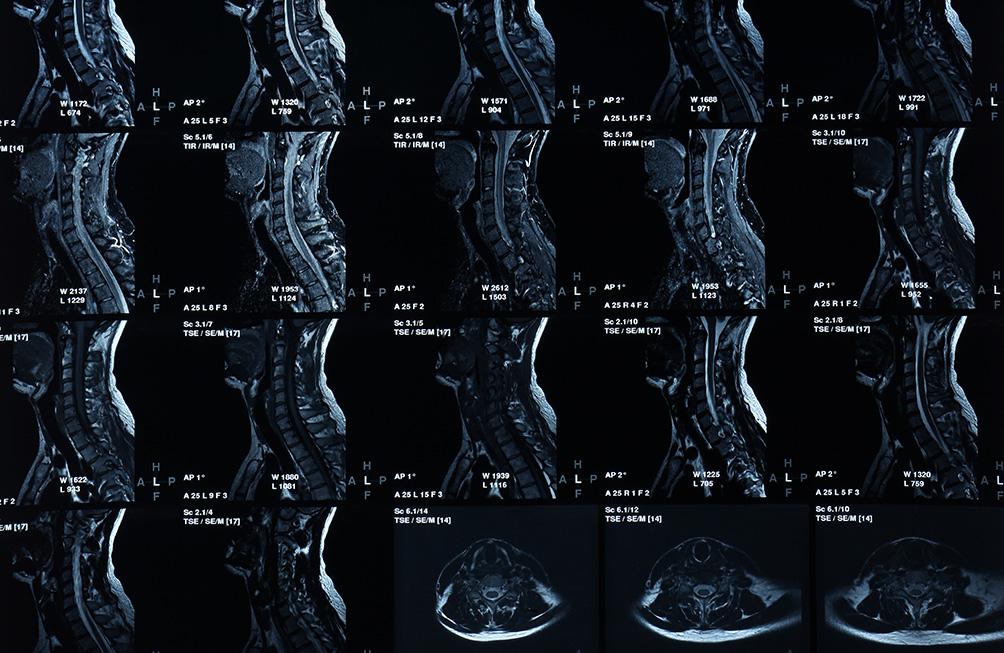

L'IRM ostéoarticulaire est une méthode sûre et non invasive, réalisée afin d'explorer et d'analyser les surfaces cartilagineuses et osseuses, ainsi que les structures ligamentaires et tendineuses.